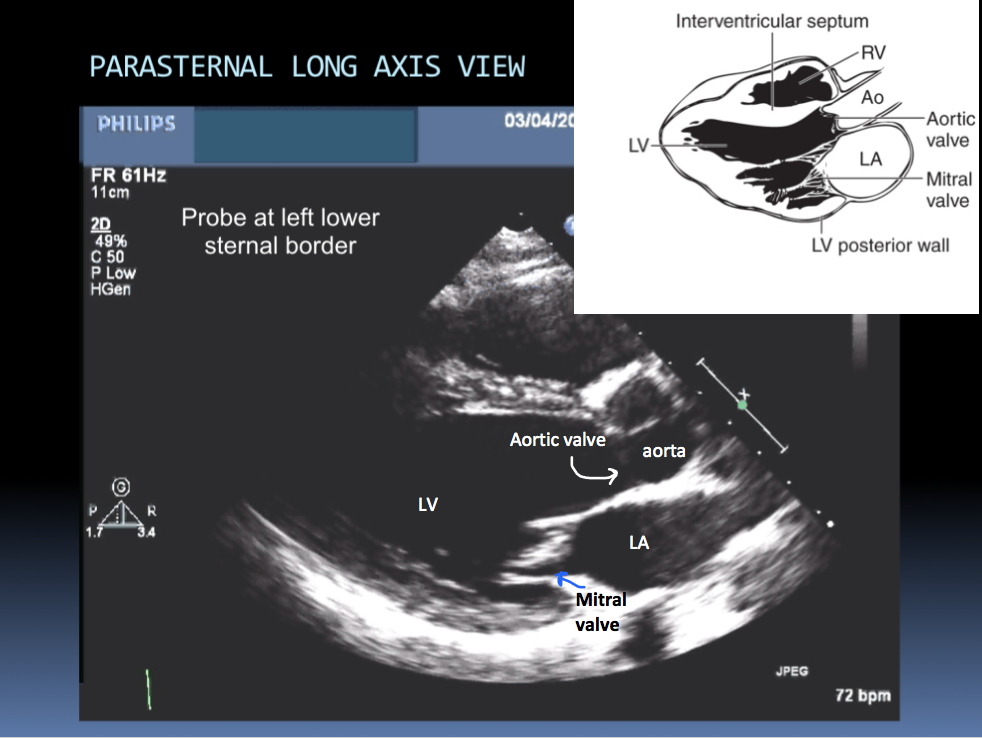

Have 2 primary probe positions, with multiple angulations (multiple ultrasonic beams are transmitted from transducer through a wide arc). The returning signals are integrated to produce 2D images of the heart on a video monitor.

Identify the chambers shown in this image: